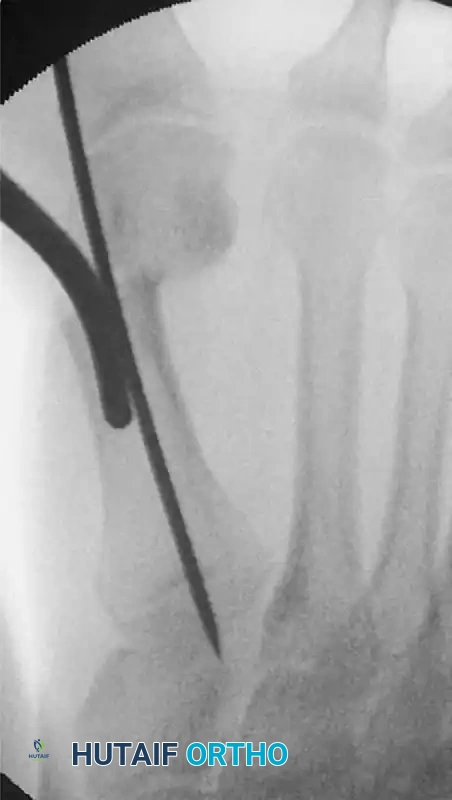

- Use a mallet to drive a stout Kirschner wire (typically 2.0 mm) from distal to proximal, entering the medial aspect of the distal fragment and passing into the medullary canal of the first metatarsal.

- To ensure absolute biomechanical stability, drive the wire as far as the base of the first metatarsal, engaging the dense cancellous bone proximally.

FIGURE 81-36 Percutaneous distal metatarsal osteotomy. The Kirschner wire is driven firmly as far as the base of the first metatarsal to improve stabilization.